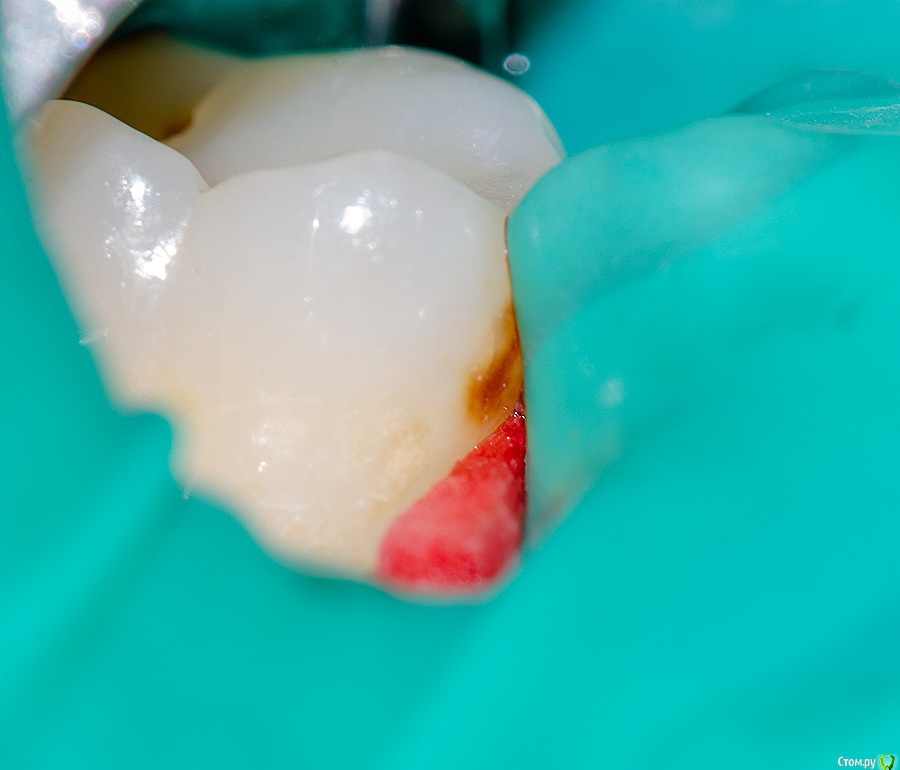

Kolchanov Опубликовано 16 июня, 2018 Поделиться Опубликовано 16 июня, 2018 (изменено) Если по rg только в эмали или вообще без изменений, то специально не трогаю. Рекомендация улучшения гигиены ниткой и все. Если обнаруживается на контакте при препе соседа, то, чаще всего, убираю.Сложнее во фронте. Вроде и лезть оснований нет, и оставлять пигментацию неохота. Тогда пробую отбелить локально. Изменено 16 июня, 2018 пользователем Kolchanov 3 Ссылка на комментарий

Тань Опубликовано 16 июня, 2018 Поделиться Опубликовано 16 июня, 2018 Если по rg только в эмали или вообще без изменений, то специально не трогаю. Рекомендация улучшения гигиены ниткой и все. Если обнаруживается на контакте при препе соседа, то, чаще всего, убираю.Сложнее во фронте. Вроде и лезть оснований нет, и оставлять пигментацию неохота. Тогда пробую отбелить локально.А когда убираете,только изменение ткани убираете или какую то форму придаёте? Ссылка на комментарий